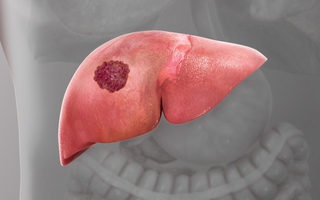

Tại Việt Nam, ung thư gan có tỷ lệ mắc đứng hàng đầu. Tỷ lệ tử vong do ung thư gan ở mức cao do đa phần các bệnh nhân phát hiện bệnh ở giai đoạn muộn.

Bệnh này tiến triển thầm lặng, ở giai đoạn sớm người bệnh thường không có triệu chứng, do đó đa số được phát hiện khi bệnh đã trở nặng.

Đến năm 2040, số người mắc hoặc tử vong do ung thư gan trên toàn cầu sẽ tăng hơn 50% nếu thế giới không nỗ lực hơn nữa để phòng ngừa căn bệnh này.

Ung thư gan là căn bệnh ung thư có tỷ lệ mắc cao nhất tại Việt Nam. Tuy nhiên, các triệu chứng ban đầu lại rất mơ hồ và khi được phát hiện thường ở giai đoạn muộn.